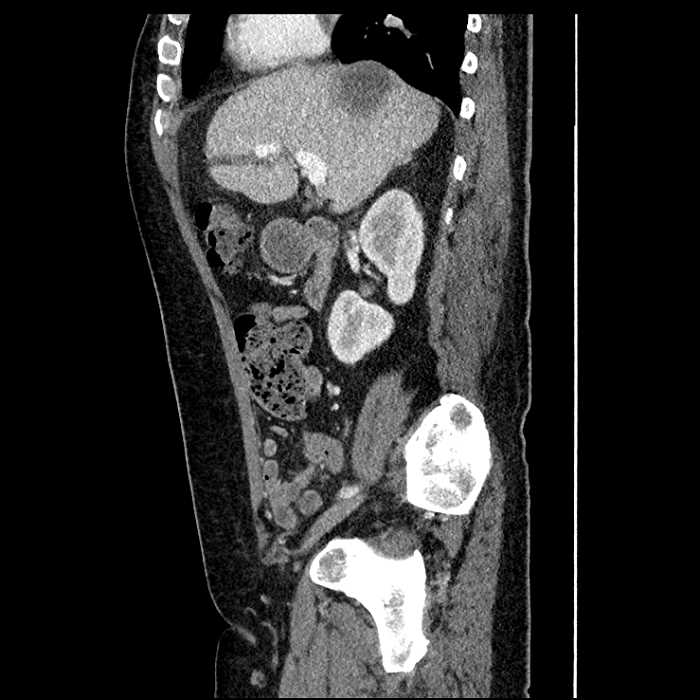

Age: 63

Sex: Male

Indication: Abdominal pain

• Large fluid density structure in hepatic segments 7 and 8 measuring 10 x 7 x 7 cm with internal septation and circumferential ill-defined low density compatible with edema

• Peripherally enhancing subcapsular collections along the anterior margin of the left hepatic lobe measuring 3 x 1 cm and 2 x 1 cm

• Clearly marginated fluid density structure in segment 7 and several other scattered tiny hypodensities, which likely represent cysts

• High grade stenosis of the left common iliac artery, with the left internal and external iliac arteries remaining patent

• Hepatic abscess

Acute sigmoid diverticulitis complicated by a small contained perforation and a large abscess in the right hepatic lobe. Additional small subcapsular abscesses along the anterior margin of the left hepatic lobe.

High grade stenosis of the left common iliac artery. The left external and internal iliac arteries are patent.